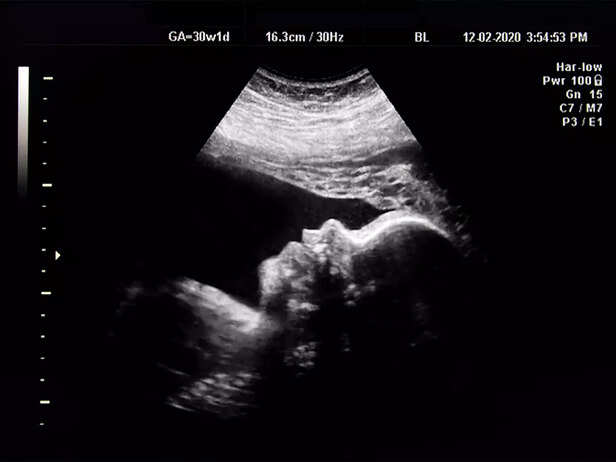

The fetal anomaly scan is a significant milestone during pregnancy, offering a look at your growing baby's development. This ultrasound examination is typically conducted between 18 and 22 weeks of pregnancy. It provides valuable insights into your baby's health, growth, and well-being. In this guide, we will look into what to expect during the scan, its significance, and how to prepare for this crucial examination. Whether you are a first-time parent or experienced in pregnancy, understanding the anomaly scan is essential to ensure a healthy journey for you and your baby.

The anomaly scan, typically conducted between the 18th and 22nd week of pregnancy, shows a glimpse into the development of your growing baby. This ultrasound allows expectant parents to see their little one's features, and doctors to assess vital organs, measure growth, and confirm the position of the placenta. With each heartbeat visualised and tiny foot counted, the bond between parent and child only deepens.